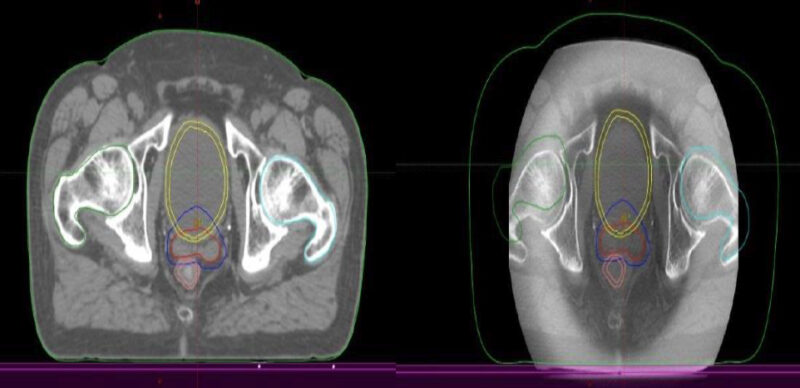

Se presentan figuras de un caso clínico de nuestro centro. Paciente de 57 años, APE: 6.5, Biopsia Gleason 7 (3+4) 2/6 sextantes. Etapificación (-), Rechaza cirugía.